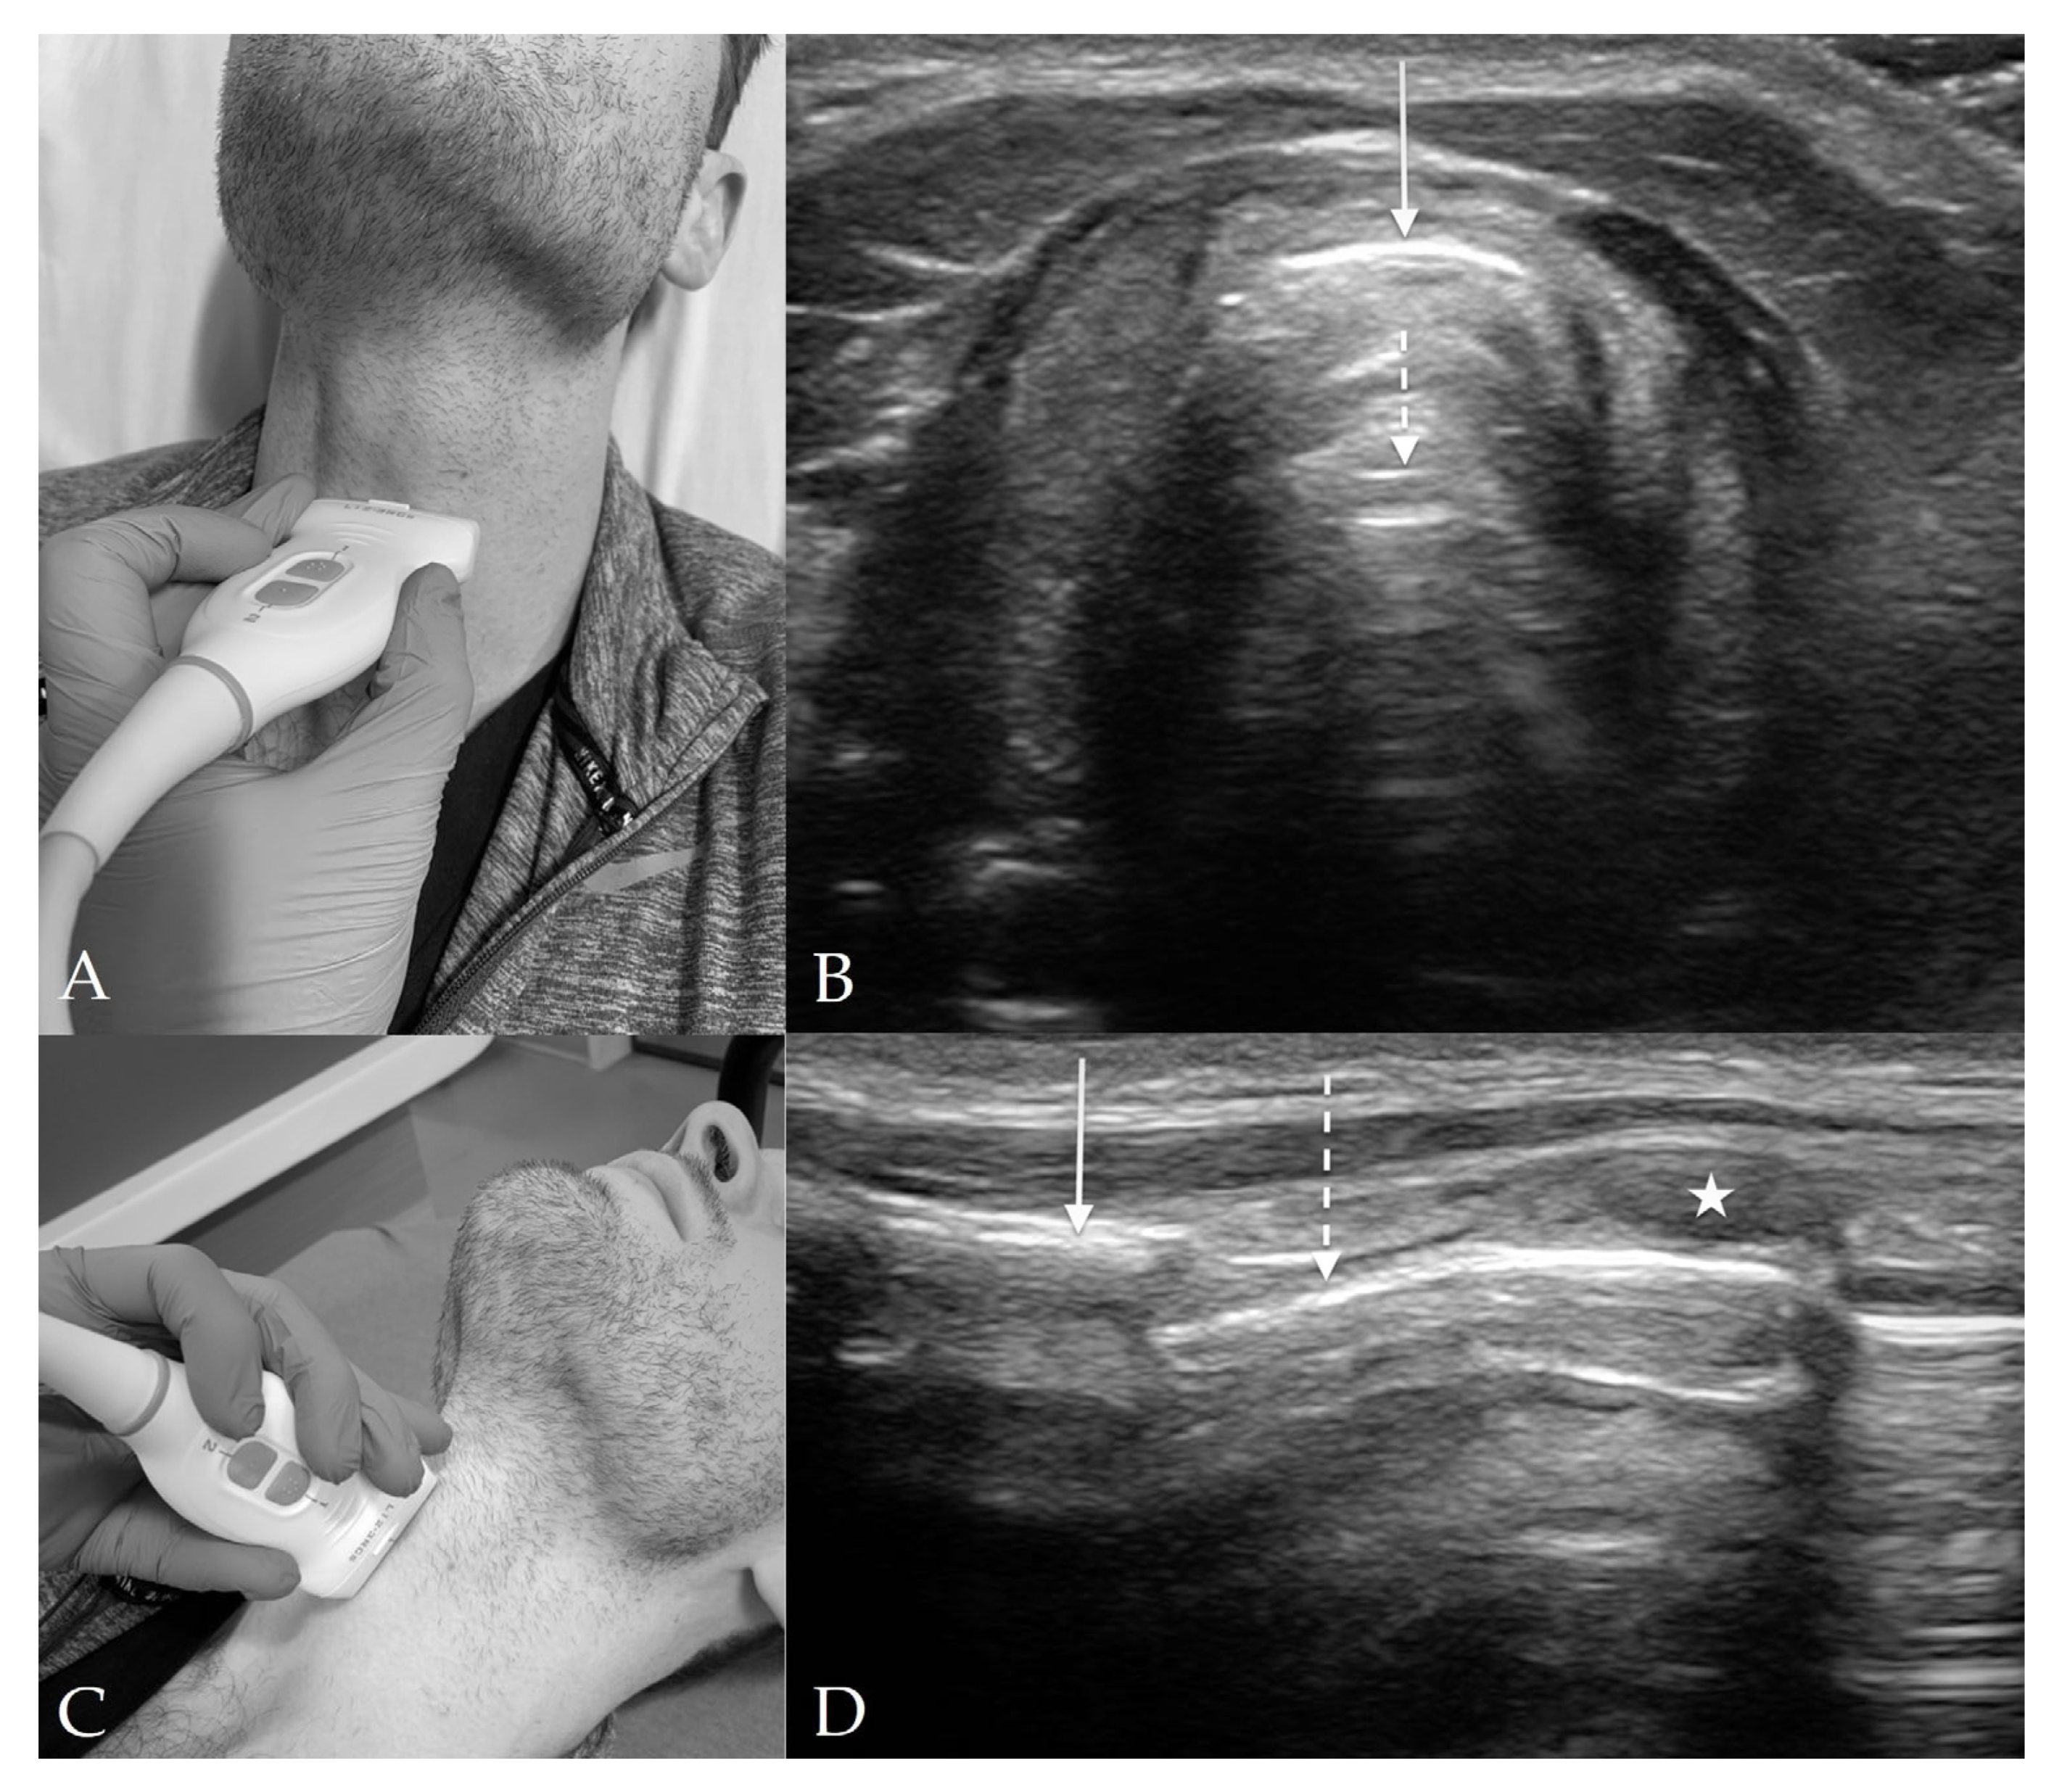

4.4. Cricothyroid View

4.5. Suprasternal View

8. Preparation for Cricothyrotomy